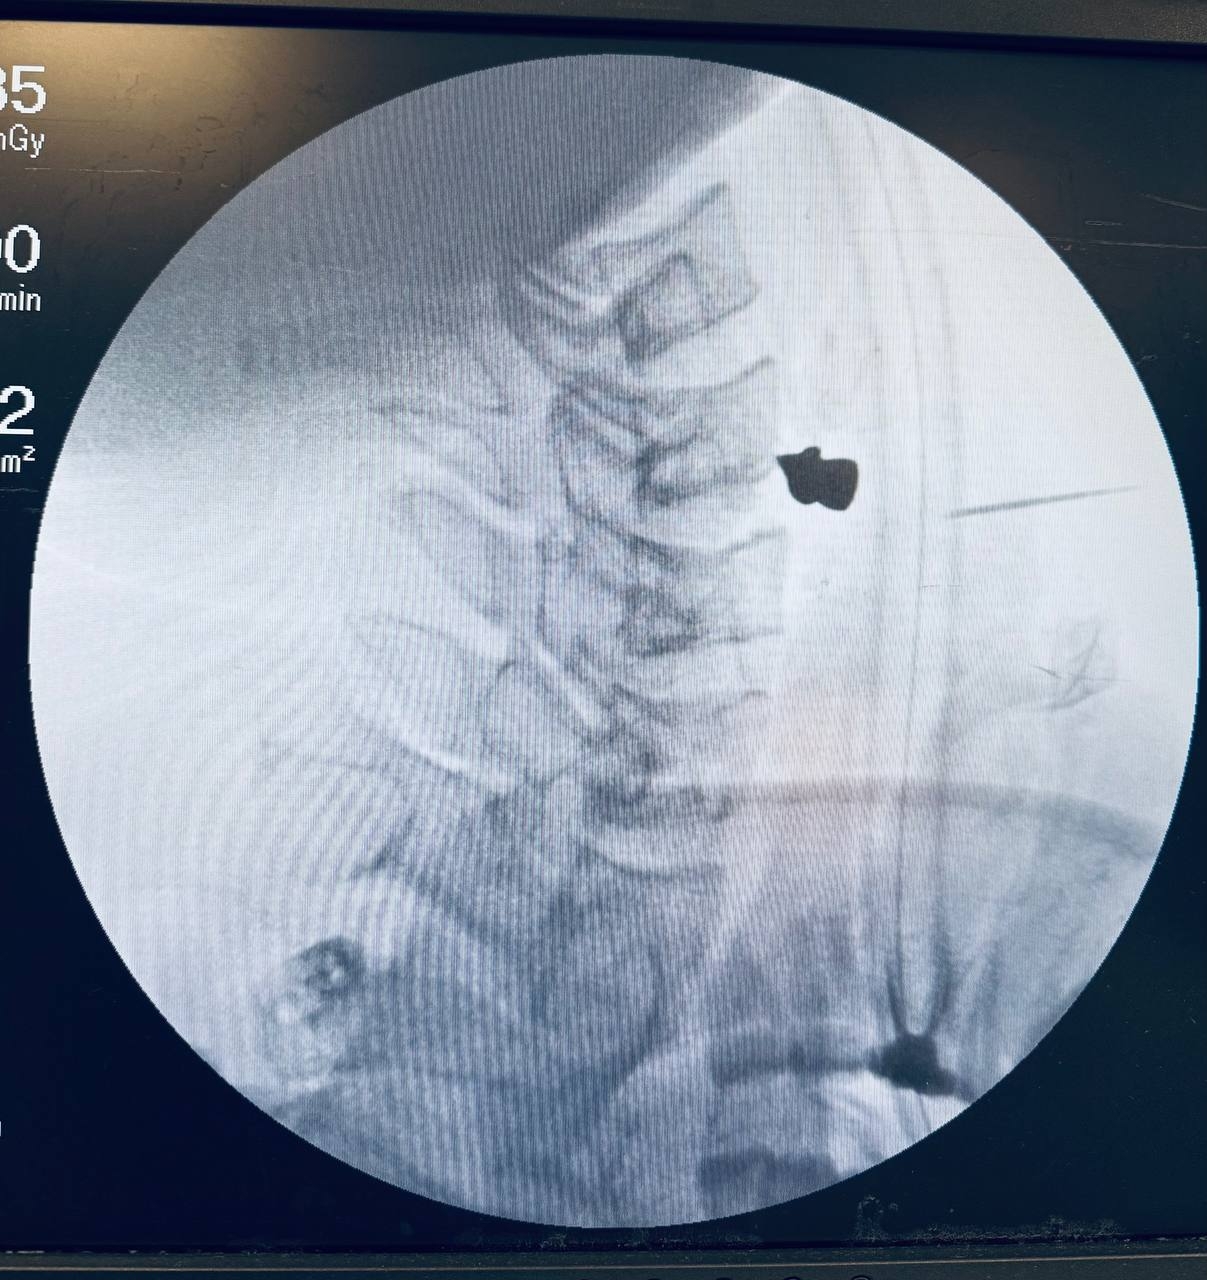

На момент поступления в РКБ пациенту было трудно глотать и говорить. Компьютерная томография показала, что ни артерии, ни трахея, ни пищевод задеты не были – пуля каким-то чудом прошла через шею и остановилась в позвоночнике. Врачи аккуратно извлекли ее и зашил рану. Вся операция заняла 20 минут. Сейчас пациент восстанавливается, будучи в палате лечебного учреждения.